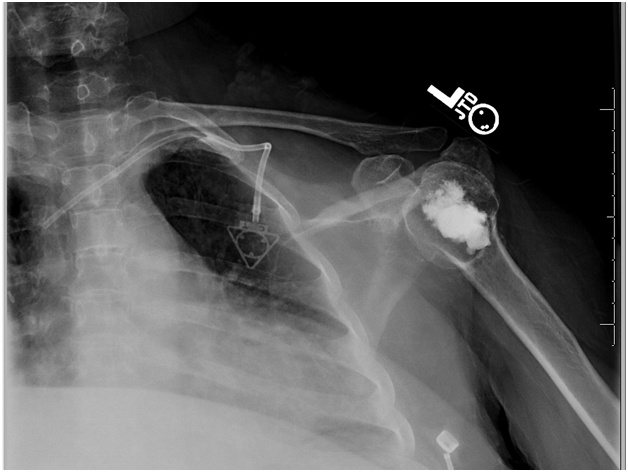

The patient was offered a percutaneous balloon cementoplasty procedure to treat her osteonecrosis palliatively as a less invasive alternative to an arthroplasty. The patient understood that this indication was not FDA approved, but was based on the success that kyphoplasty has shown in treating vertebral compression fractures. She willingly consented to the procedure. She was placed supine on the operating table and under fluoroscopic guidance a Jamshidi needle was advanced into the humeral head. A guide wire was then placed followed by a Kyphon trochar. A drill was advanced to within 2mm of the subchondral collapse and a Kyphon balloon was placed. The pressure was elevated to approximately 300cc of mercury. The balloon was then removed and 7.5mL of cement was injected into the humeral head (Figure 3). The procedure was repeated on the left side in which 7mL of cement was injected (Figure 4). The patient was successfully extubated and in stable condition following the procedure. The patient was intubated for less than 2 hours in total and was able to be dischared the same day.

Figure 3 Post cementoplasty right shoulder radiograph revealing cement filling the void created by the kyphoplasty balloon. Assessment of the articular surface is difficult in this radiograph due to the angle of the beam.

Figure 4 Post cementoplasty radiograph of the left shoulder revealing cement in place in the humeral head.